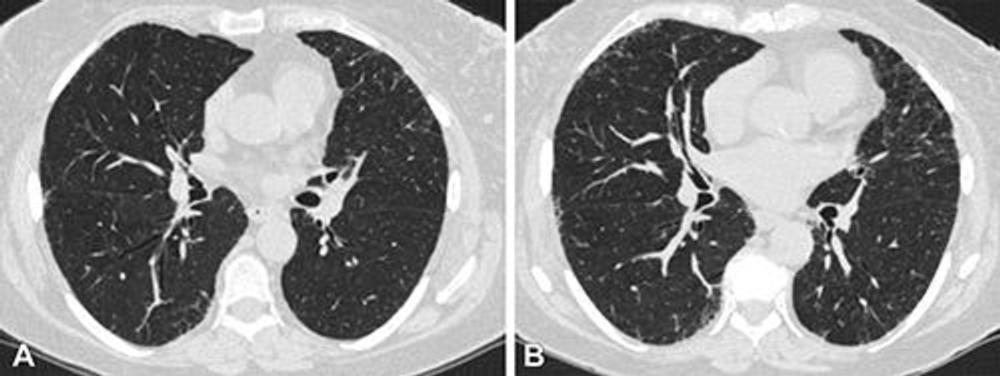

Figure 2. Axial chest CT scans at (A) visit 1 and (B) visit 2 at the level of the takeoff of the right middle bronchus of a participant with 1.2 annual percentage quantitative interstitial abnormality progression. The female participant was 62 years old at visit 1 and 67 years old at visit 2 and a current smoker at both visits, with a 47.5 pack-year history at visit 2. This participant had four subsequent acute respiratory disease (ARD) events and three subsequent severe ARD events.